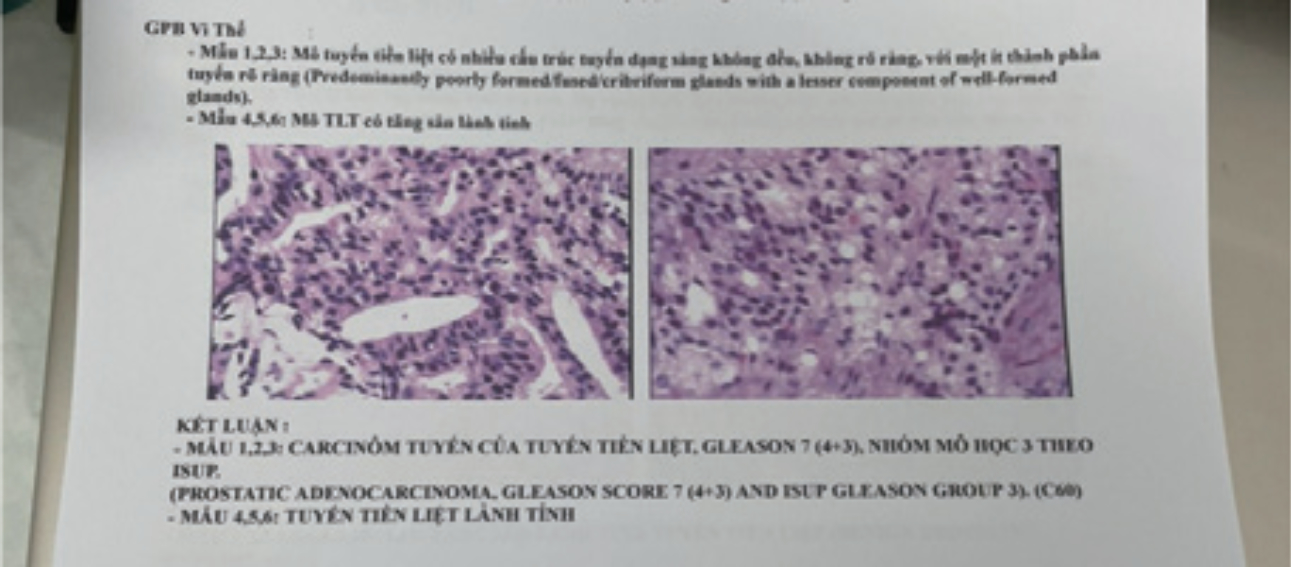

Biopsy Result:

A 6-core biopsy was done. Tissue sample numbers 1 to 3 were taken from the right lobe, and numbers 4-6 were taken from the left lobe.

?

The Biopsy Results Were

1,2,3: PROSTATIC ADENOCARCINOMA, Gleason score 7 (4+3), ISUP Gleason group 3 (C60): predominantly poorly formed/fused/cribriform glands with a lesser component of well-formed glands.

4,5,6: Normal prostate tissue.